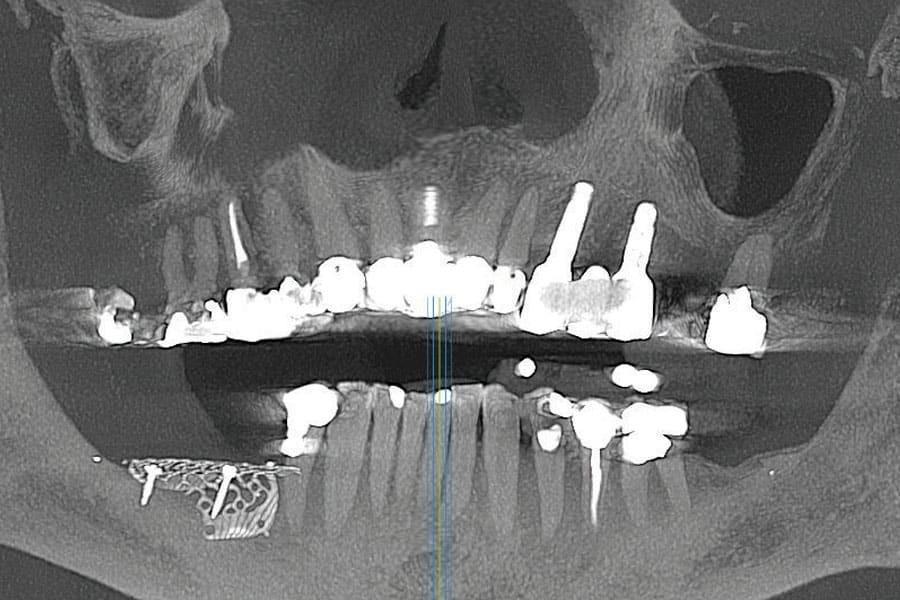

Панорамный рентгеновский снимок, полученный на основе КЛКТ, показал скошенный вертикальный дефицит костной ткани в правом боковом отделе нижней челюсти с недостаточной высотой кости для установки дентальных имплантатов выше нижнего альвеолярного нерва (Фото 1). КЛКТ левого верхнечелюстного квадранта выявила разрушенный левый клык с достаточным объемом кости для установки имплантатов в области клыка и второго премоляра.

Фото 1. Предоперационный панорамный рентгеновский снимок, полученный на основе КЛКТ, демонстрирующий вертикальную атрофию кости в правом боковом отделе нижней челюсти.